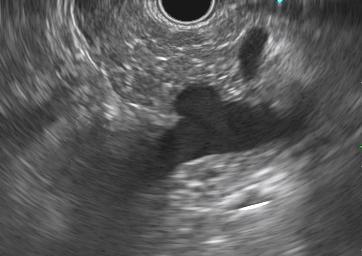

El diagnóstico se realiza preferiblemente mediante tomografía computarizada, con hallazgos característicos como un ángulo aortomesentérico menor de 22° y una distancia entre vasos menor de 8 mm (25). La endoscopia digestiva alta puede ser útil en las etapas iniciales, aunque por sí sola no es concluyente. Kim et al. (26) describieron tres hallazgos endoscópicos indirectos sugestivos de pinzamiento aortomesentérico:

- Compresión pulsátil vertical u oblicua en la tercera porción del duodeno con una expansión luminal inferior al 30 % incluso tras una insuflación continua durante 15 segundos

- Dilatación del duodeno proximal

- Presencia de secreción biliar en la cavidad gástrica